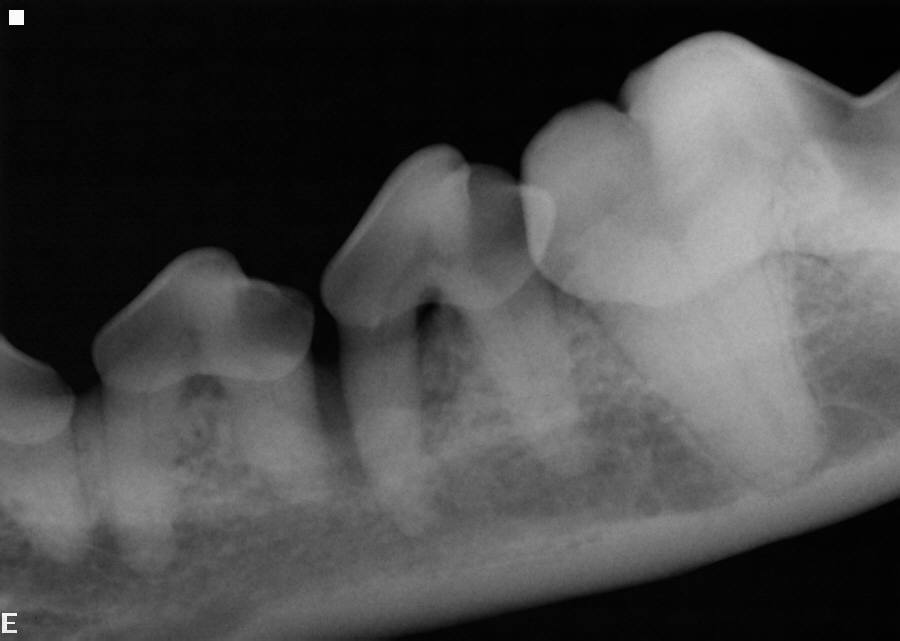

Dental X-ray Right Bitewing